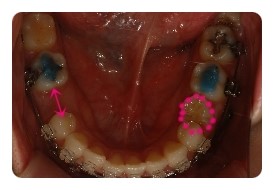

( 하악비교 )

▲ 발치전 - 왼쪽결손치, 오른쪽유치 1차삭제 예정

▲ 5월 - 스크류식립 후 본격적으로 하악당기기 1개월차

▲ 7월 - 3개월차, 오른쪽유치 2차삭제

▲ 10월 - 6개월차

물론 사진크기나 각도가 100% 일치하진않지만 최대한 비슷하게 비교해보려고 노력햇는데

어떤가요 ??

왼쪽 결손치는 발치한지 몇년되엇기때문에 이미 잇몸뼈가 굳어져서 진행이 더딜수밖에 없다고해요

그동안 꿈쩍도 안하고잇는줄 알앗는데 비교해보니 이정도면 뭐 기특하네요 ㅋㅋ

그에비해 오른쪽 유치는 조금씩 삭제하면서 당기고 잇는데요

쑥쑥 잘 움직여주고 잇어서 2차 삭제까지 햇는데도 벌써 또 닫혀가고 잇어요

아마도 다음에 가면 또 삭제할듯요 ;; 아 ~~~ 삭제할때의 시큰시큰한 느낌 시르다 ㅠㅠ